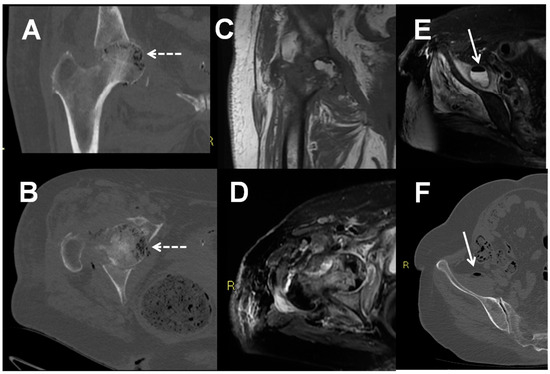

- De Vuyst, D.; Vanhoenacker, F.; Gielen, J.; Bernaerts, A.; De Schepper, A.M. Imaging features of musculoskeletal tuberculosis. Eur. Radiol. 2003, 13, 1809–1819. [Google Scholar] [CrossRef]

- Sharif, H.S.; Morgan, J.L.; Al Shahed, M.S.; Al Thagafi, M.Y. Role of CT and MR imaging in the management of tuberculous spondylitis. Radiol. Clin. N. Am. 1995, 33, 787–804. [Google Scholar]

- Ridley, N.; Shaikh, M.I.; Remedios, D.; Mitchell, R. Radiology of skeletal tuberculosis. Orthopedics 1998, 21, 1213–1220. [Google Scholar] [CrossRef] [PubMed]

- Hong, S.H.; Kim, S.M.; Ahn, J.M.; Chung, H.W.; Shin, M.J.; Kang, H.S. Tuberculous versus pyogenic arthritis: MR imaging evaluation. Radiology 2001, 218, 848–853. [Google Scholar] [CrossRef]

- Sharma, P. MR features of tuberculous osteomyelitis. Skeletal. Radiol. 2003, 32, 279–285. [Google Scholar] [CrossRef]

- Naselli, N.; Facchini, G.; Lima, G.M.; Evangelisti, G.; Ponti, F.; Miceli, M.; Spinnato, P. MRI in differential diagnosis between tuberculous and pyogenic spondylodiscitis. Eur. Spine J. 2021. [Google Scholar] [CrossRef]